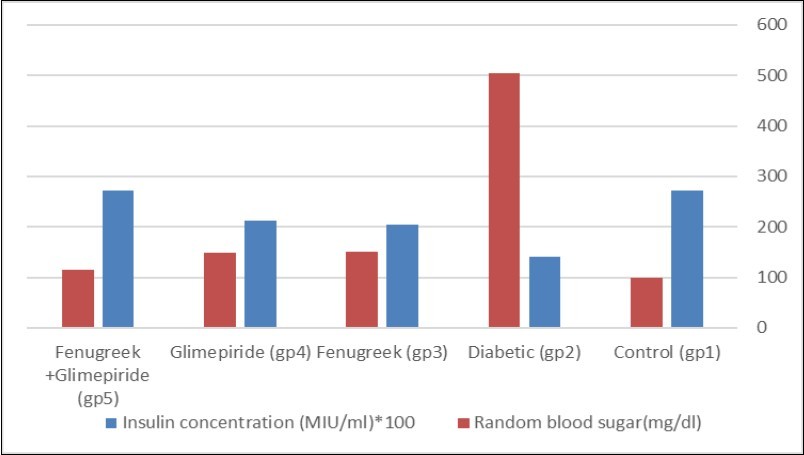

Random Blood Sugar Level

The current study showed some changes in the biochemical measurements due to the injection of Streptozotocin (Figure 2). Group (5); Fenugreek and Glimepiride combination improved the random blood sugar to reach a value near the normal control values. The random blood sugar level of group (3) and group (4) showed no significant difference from each other. Injection with STZ induces activation of poly adenosine diphosphate ribosylation and nitric oxide release. As a result, pancreatic cells are destroyed by necrosis 15. Fenugreek seeds water extract acts as an insulin secretor. Hypoglycemic effect of Fenugreek may be mediated through stimulating insulin synthesis and increasing β pancreatic cells secretion. The primary mechanism of action of Glimepiride in lowering the blood glucose appears to be dependent on stimulating the release of insulin from functioning pancreatic beta-cells 16. Glimepiride binds to sulfonylurea receptors on β-cells leading to blocking of K+ ATP channels, opening of voltage-gated calcium channels and increase in Ca2+ influx leading to insulin release from pancreatic β-cells.

Figure 2.Effect of Effect of Fenugreek and Glimepiride on random blood sugar level and insulin concentration of diabetic male albino rats.

Insulin Concentration

The present study demonstrated that STZ injection induced a significant decrease in the concentration of insulin in serum when compared with the control values. Groups (3 and 4) showed partial improvement in the concentration of insulin when compared with STZ group. However, the insulin concentration of group (5) reached the same value as the control group values (Figure 2).